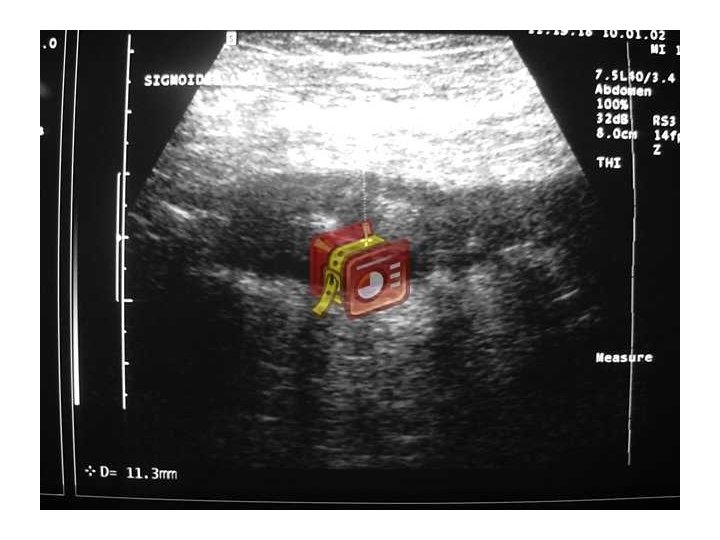

Diverticulitis • Inflamación divertículo y tejido pericolónico • 10 a 20% de los pacientes que conocen su enfermedad la desarrollan • Clínica: A veces pobre en el anciano – Dolor intenso abdominal (FII), irritación peritoneal, fiebre, abdomen quirúrgico. Leucocitosis – Perforación: absceso, neumaturia, fístulas • En diagnóstico útil Ecotomografía y TAC • Colonoscopía en frío confirmar patología y descartar neoplasia • 22– 30% de los individuos que presentan un primer episodio de diverticulitis presentarán un segundo episodio

Divertículos de colon